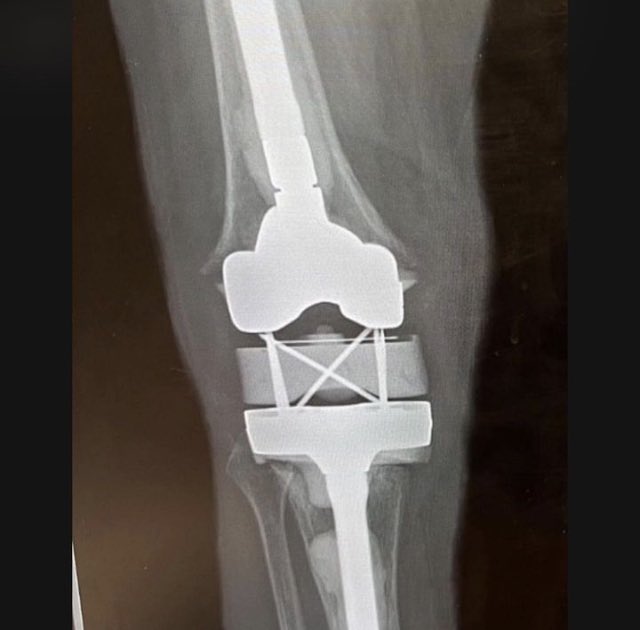

@aschwartz45 @generalorthomd Those are tm modular sockets, not continuum. Will need trilogy liners